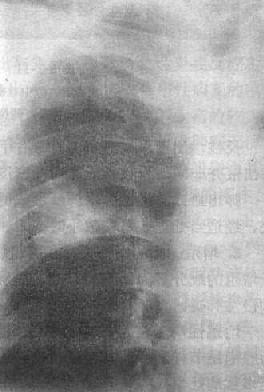

图3-1-10 渗出性病变

两肺浸润型肺结核,两肺第1~2前肋间出现边

缘模糊、密度不太高的云絮状影